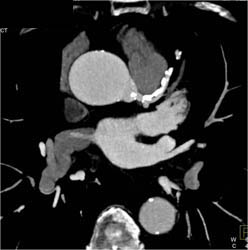

Normal Aortic Valve